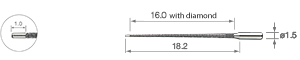

• für Wurzelkanalspülung 17 mm

• Packung à 3 St.

• für Wurzelkanalspülung 23 mm

• Packung à 3 St.

• für Wurzelkanalspülung 26 mm

• Packung à 3 St.

• für Wurzelkanalspülung 32 mm

• Packung à 3 St.